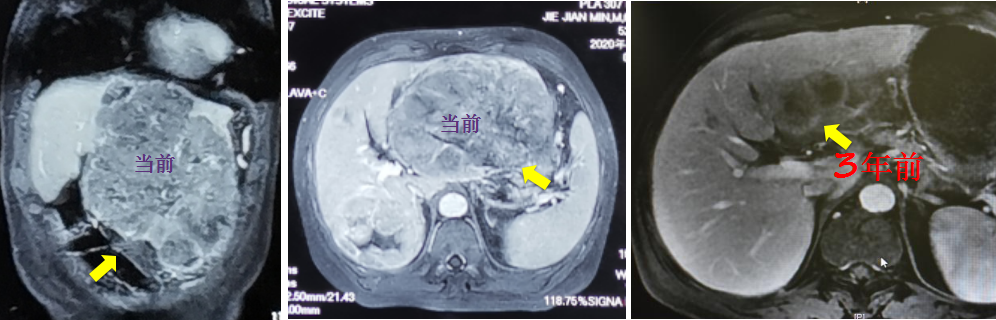

患者刘先生72岁,有多年的酗酒史,后因常规查体,在医院被确诊为早期小肝癌。刘先生害怕手术带来的创伤和疼痛,选择保守治疗。迷信“偏方”治疗3年后,肿瘤越长越大,挤压到胃等脏器,以致刘先生连吃饭都吃不下。此时刘先生才想接受手术,但切除难度和手术风险已变得极大,多方求医均被告知无法手术。

最终,刘先生慕名来到北京清华长庚医院,经过系统全面的评估,没有发现肝脏以外的远处转移,同时剩余肝体积也能满足身体需求,因此接受了近乎生理极限的“扩大左半肝切除联合右后叶肿瘤局部切除”。术后,在医生指导下,刘先生正在进行后续的防复发治疗,目前术后半年,身体状态良好。

杨世忠特别强调,这个患者发现肝癌后“耽误”了3年时间,没有发生远处转移和肝内的广泛扩散,属于比较少见的情况,而大多数患者是没有这样幸运的。

针对曹先生,清华长庚医院董家鸿院士团队为其制定了“放疗+靶向治疗+免疫治疗”的前期转化治疗方案。在放疗科黎功主任的主持下,经过精准放疗,患者的肿瘤明显缩小,肝静脉癌栓也消失了。然后,肝胆外科杨世忠接手了后续的外科治疗,为患者实施了持久美兰染色引导的精准右半肝切除。目前,术后1年,患者生活状态正常。